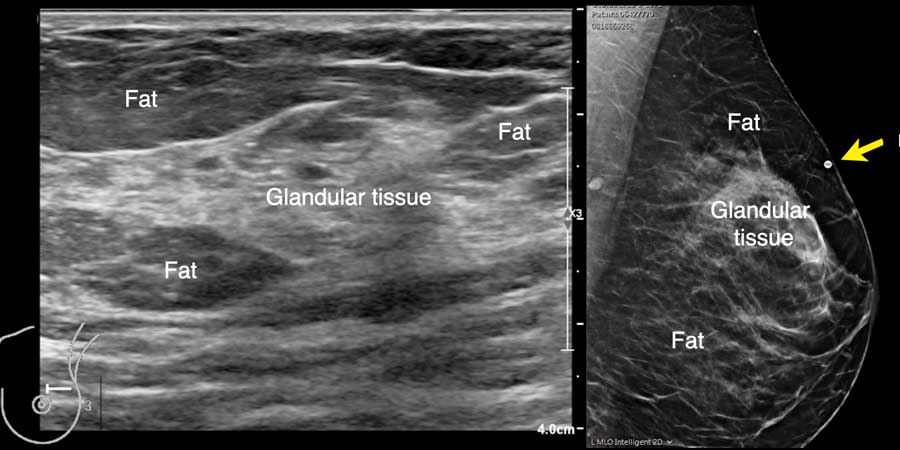

Đây là hình ảnh siêu âm bình thường của tuyến vú.

Lớp xám phía trên là da.

Tiếp theo là sự pha trộn giữa mô mỡ (tối hoặc giảm âm) và mô tuyến (xám sáng hoặc tăng âm).

Lớp có vân sọc phía sau mô vú là cơ ngực.

Phía sau hoặc sâu hơn so với xương sườn có một vùng đen hay bóng cản âm phía sau.

Phổi là lớp có thể quan sát sâu nhất.

Không khí trong phổi phản xạ hầu hết sóng âm, tạo ra một đường sáng hoặc tăng âm với bóng cản bẩn phía sau.

Thành phần mô vú

Siêu âm cho phép xác định thành phần mô vú: mô xơ tuyến đồng nhất – mô không đồng nhất – hoặc mô mỡ đồng nhất (hình).

Lưu ý rằng hình ảnh nhũ ảnh và siêu âm rất tương đồng nhau.

Trong cùng một tuyến vú có thể tồn tại các vùng có nhiều mô mỡ xen kẽ với các vùng chủ yếu là mô xơ tuyến, như có thể thấy trên video.

Khi quan sát đường bờ của mô tuyến (mũi tên), có thể hình dung rằng khi sờ nắn sẽ cảm thấy gồ ghề và đôi khi tạo cảm giác như có một khối u khi mô tuyến rất phát triển.